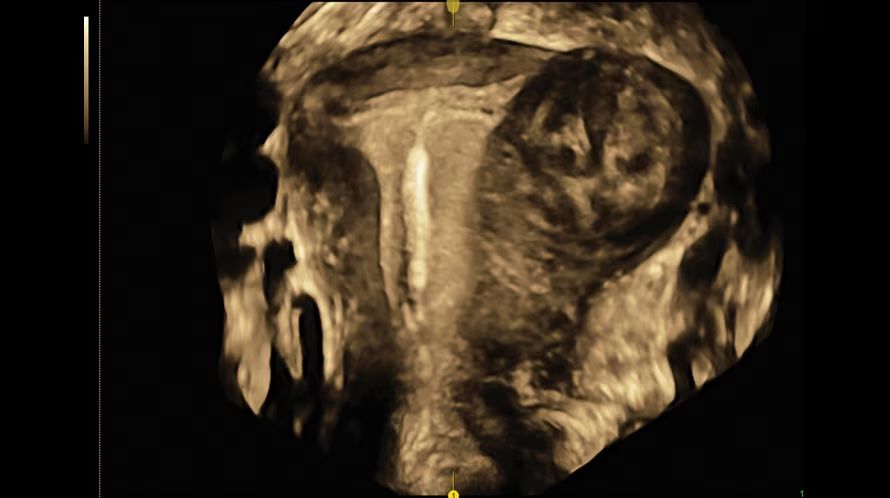

- HDlive - cемейство технологий Voluson для глубинного понимания анатомии и дифференцировки структур в объеме с беспрецедентной реалистичностью. На изображении кистозное образование яичника, реконструкция с использованием технологии HDlive Studio.